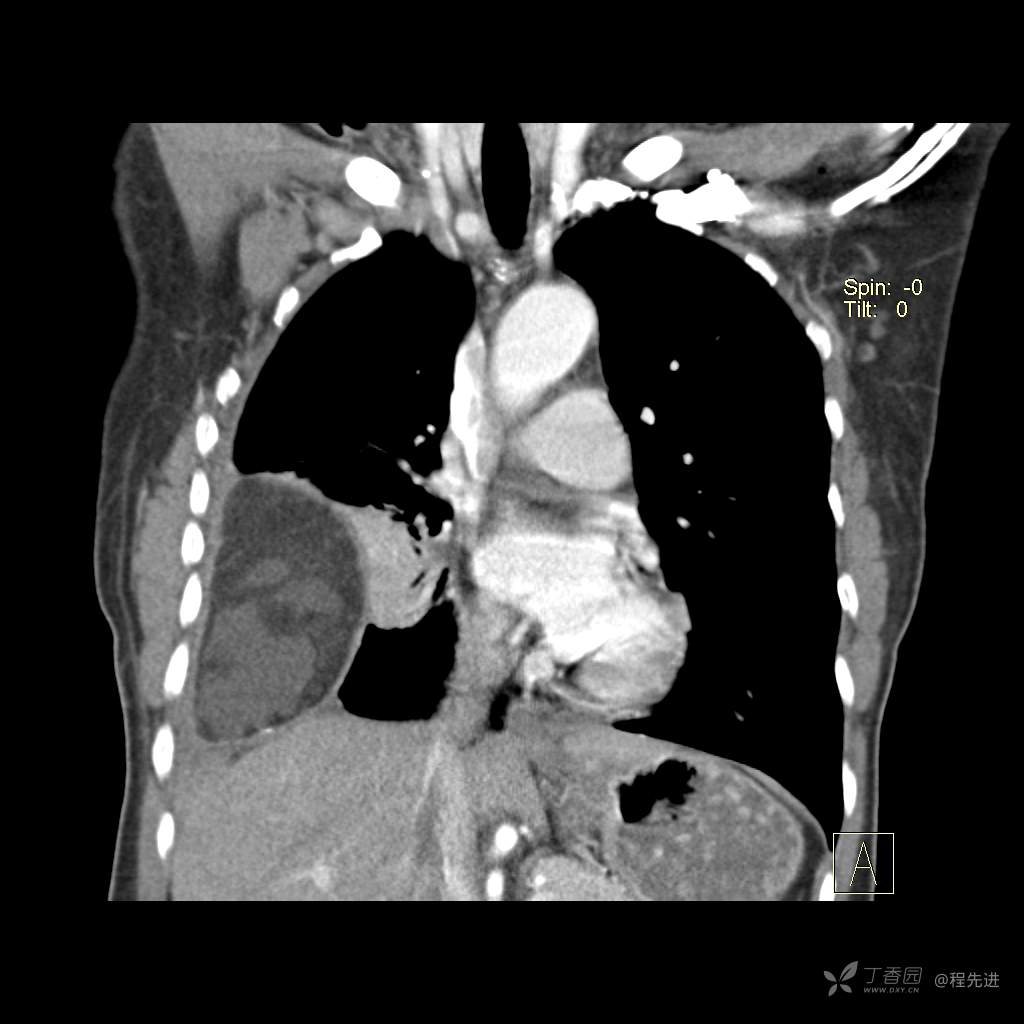

患者性别:女

患者年龄:51岁

简要病史:胸闷半年